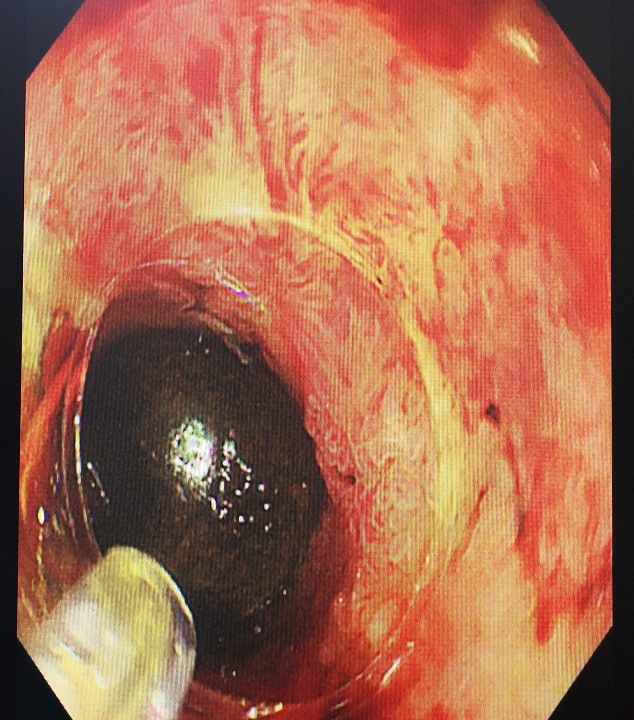

在麻醉科团队的有力保障下,手术由消化内科内镜诊疗团队中曾伟副主任医师主刀实施,张鸣青主任医师全程指导。在使用特殊器械逐层切开胃壁后,消化内镜经胃切口进入腹腔并顺利找到胆囊,小心切开胆囊壁后进入胆囊探查,发现黑色结石1枚及胆囊息肉数个。术中在顺利套取出巨大黑色结石后,亦将胆囊息肉钳除,术后夹闭胆囊及胃壁切口,并留置胃肠减压管进行胃肠减压。术后,曾伟副主任医师就术中情况及术后注意事项向患者家属进行了说明。患者术后两天病情平稳,未出现腹痛、发热等并发症,已顺利拔除胃肠减压管,并逐渐恢复正常饮食。